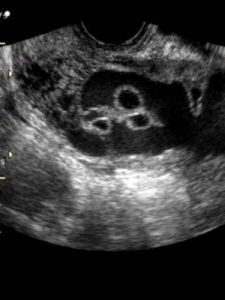

近年開展的AQ(超聲聲學定量技術)、CK(彩色寶壁運動成像技術)技術可用於心內膜自動描記,方便的觀察心臟室壁運動。心臟超聲軟體也十分豐富。有些高檔次心臟彩超可以報告川多種心臟檢測參數,對臨床診斷各類心臟疾病極有價值。腹部彩超除作其它腹部臟器檢查外都裝有豐富的產科軟體,可方便的檢出胎齡,從而準確方便地判定胎兒發育狀況及報告、羊水指數及多項胎兒發育參數。高檔彩超,特別是三維彩超都裝備了變頻探頭、寬頻探頭及超聲CT軟體,使圖像更清晰更逼真,解析度更強,臨床套用更廣泛。今天的彩色超聲都卜勒所顯示的灰階和彩色圖像質量對體內流體(血液)的敏感程度均達到理想程度。所以說彩色超聲都卜勒設備的開發成功是超聲醫學發展史上的又一個里程碑。